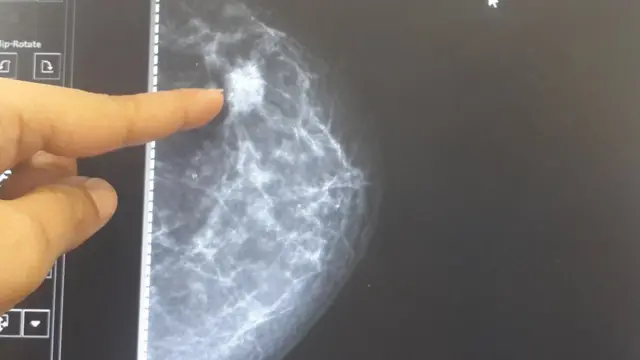

उनकी सलाह है कि ज़्यादा कोलेस्ट्रॉल वाले भोजन से दूर रहें और गर्भनिरोधक दवाइयों का सेवन ना करें. इसके अलावा 40 की उम्र के बाद साल में एक बार मेमोग्राफी ज़रूर करवाएं.

कैंसर रोग विशेषज्ञ डॉ. रेशमा पलेप के मुताबिक़, "अक्सर मेमोग्राफी टेस्ट का नाम सुनकर महिलाएं डरती हैं, लेकिन इस टेस्ट से शरीर को कोई नुकसान नहीं पहुंचता है."

डॉ आरए बडवे कहते हैं कि, "बॉयोप्सी टेस्ट से जानकारी मिल जाती है कि स्तन कैंसर है या नहीं. अगर स्तन में गांठ है तो उसका आकार कितना बड़ा है और यह किस तरह का स्तन कैंसर है ये जानने के बाद इलाज़ की प्रक्रिया आसान हो जाती है."

डॉ बडवे बताते हैं कि स्तन कैंसर की 4 अवस्था होती है. स्तन कैंसर अगर पहले स्टेज में है तो मरीज के ठीक होने की उम्मीद 80% से ज़्यादा होती है. दूसरे स्टेज में अगर स्तन कैंसर है 60-70% तक महिलाएं ठीक हो जाती हैं, वहीं तीसरे या चौथे स्टेज में स्तन कैंसर है तो इलाज़ थोड़ा कठिन हो जाता है.